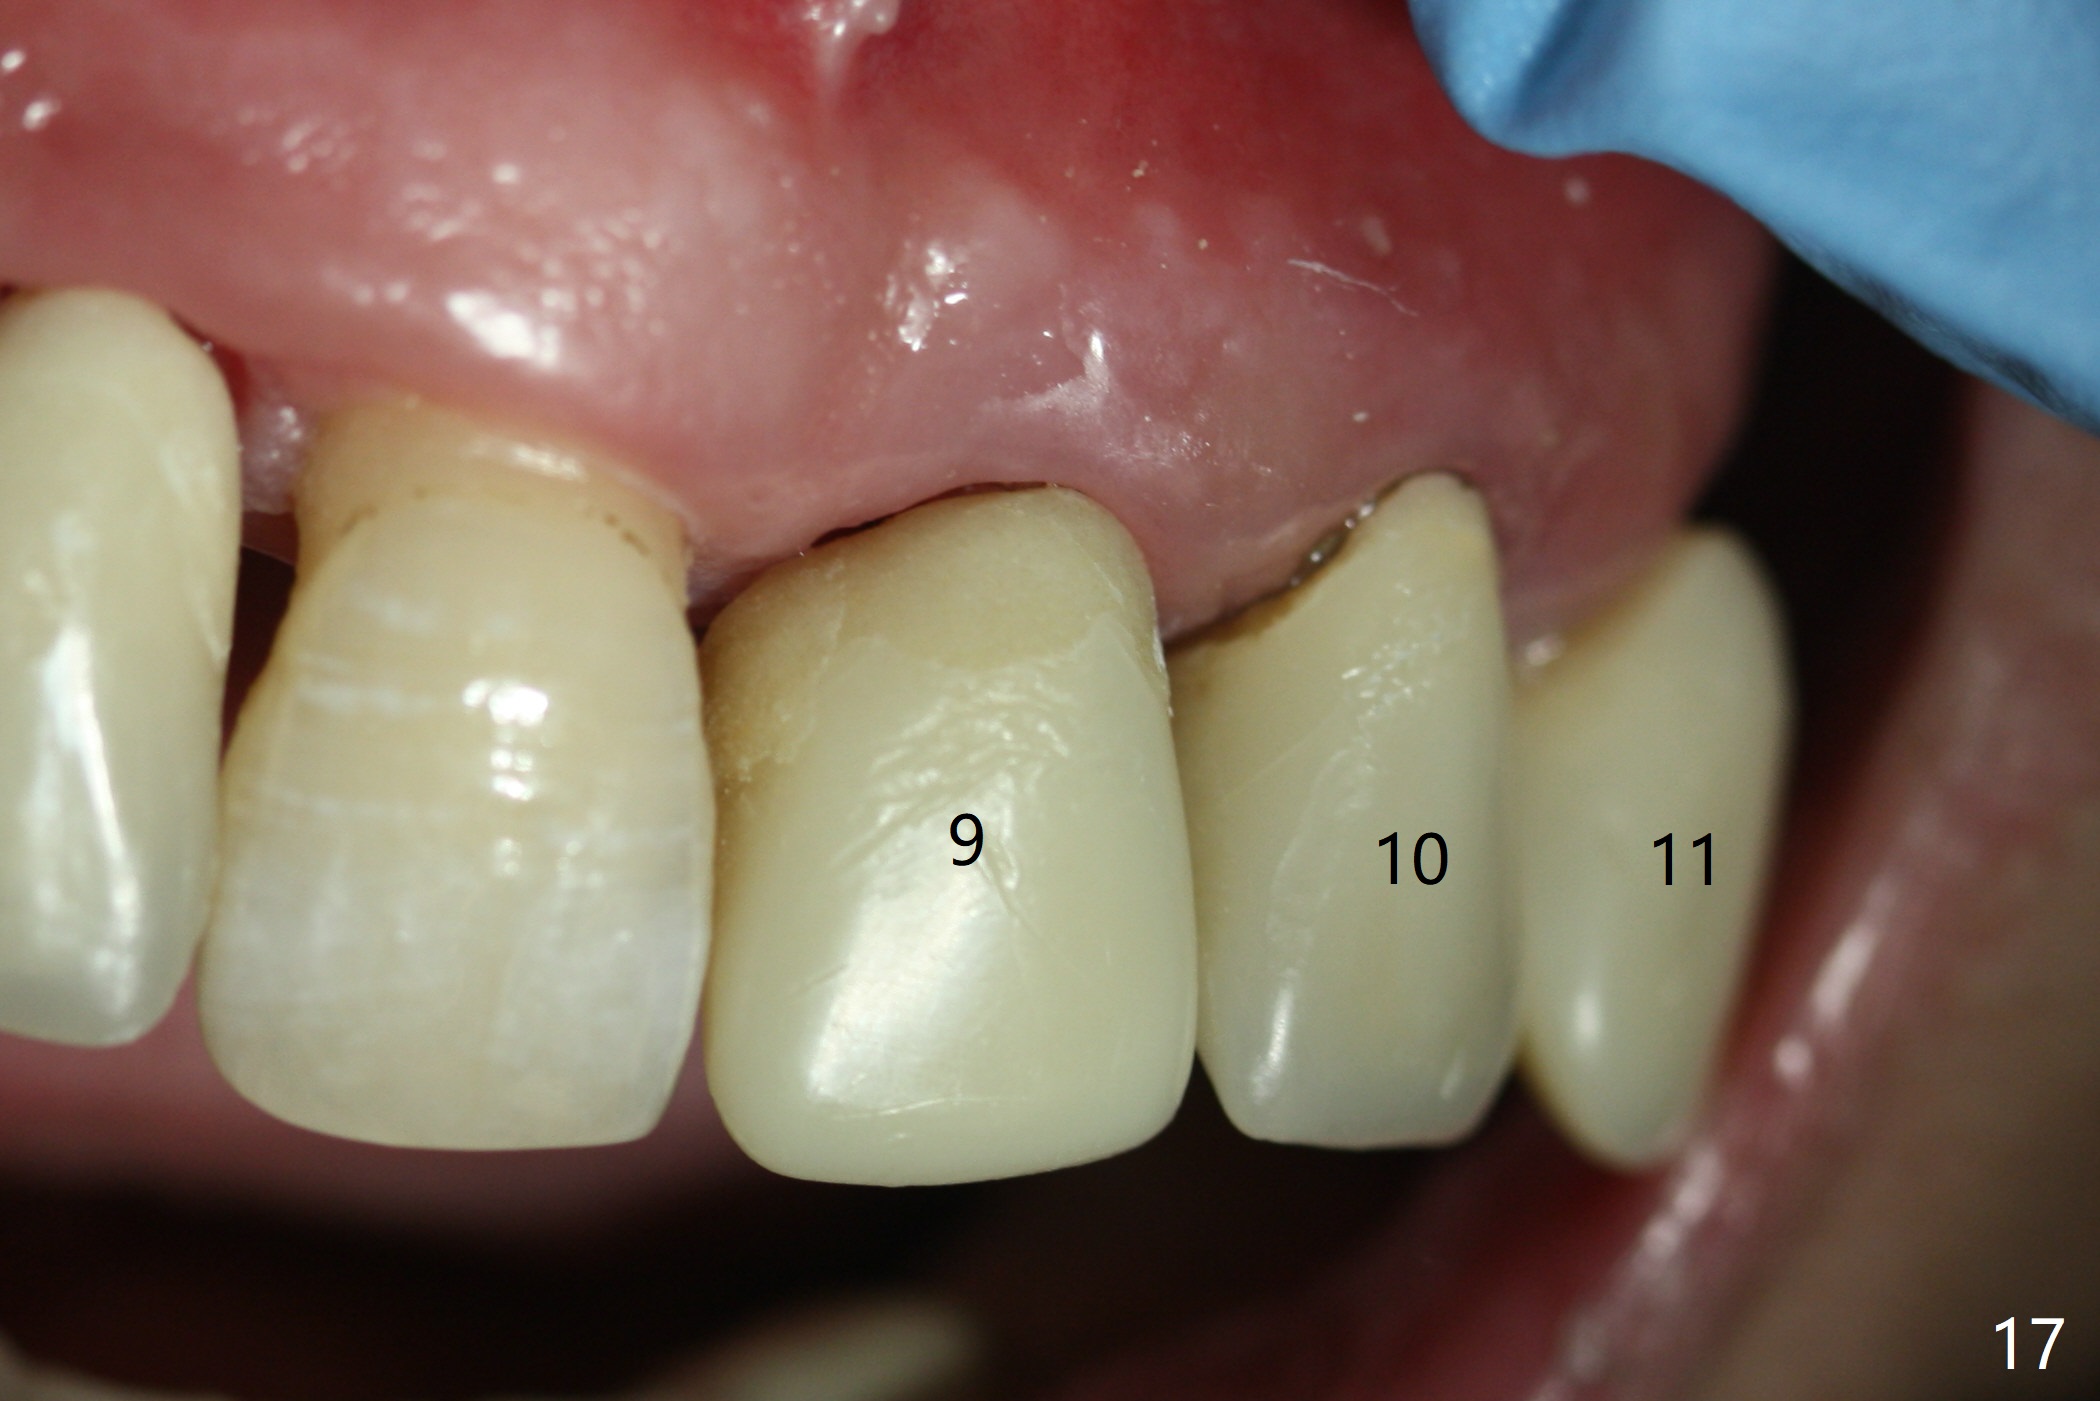

The patient returns 8 days postop, uncomfortable with overhang in the provisional (Fig.10 *). The sockets appear to be healing with loose bone graft (Fig.11) when the provisional is removed for trimming (Fig.12). Six (for #7,13) and seven (#9-11,15) months postop, the soft (Fig.13,17) and hard (Fig.14-16,18) tissues heal. It appears that the trajectory at #9,11 and 13 should be changed by using angled abutments (Fig.18,19 (panoramic X-ray taken 2 months earlier)) before provisional and final restoration.

In fact angled abutments are used at #11 and 13 (4.5x15 degree (5 mm)A) with a straight abutment at #15 (5.5x4(4) mm).